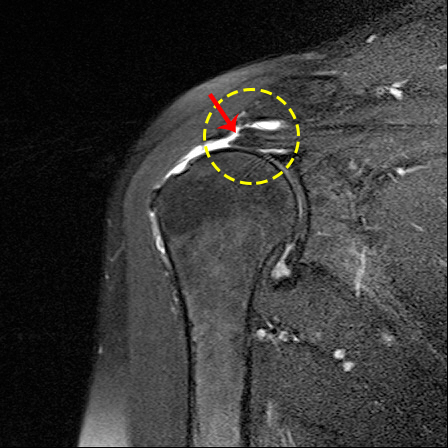

20대 젊은 층은 주로 어깨를 많이 쓰는 과격한 운동을 하다 탈구가 되는 경우가 많은데, 빨리 원위치로 돌려놓고 잘 치료하지 않으면 자꾸 재발하는 습관성 탈구가 되기 쉽다. 습관성 탈구가 반복되면 힘줄, 관절, 관절낭 등이 손상되어 통증이 심해지고 어깨의 불안정성이 커지므로 수술을 하는 것이 좋다.

반면 50대 이상은 탈구가 되어도 재발이 적다. 대신 관절 주변의 조직이 찢어지고 염증이 생겨 관절이 굳어지는 오십견으로 진행되기 쉽다. 오십견은 1~2년 지나면 자연스럽게 좋아지기도 한다. 그래서 치료를 잘 안해 어깨가 부분적으로 굳는 경우가 많다. 그 상태를 놔두면 어깨가 점점 더 굳어 인공관절 수술을 해야 할 수도 있으니 적극적으로 물리치료나 약물치료를 하는 것이 좋다.

물론 어깨가 많이 굳어 통증이 심하고 일상생활이 불편하면 인공관절 수술을 해야 한다. 최근에는 어깨 인공관절 수술을 많이 하는 추세지만 어깨 인공관절 수명은 아직까지 15년 정도에 불과하다. 무릎 인공관절이 평균 20년, 고관절이 30년인 것과 비교하면 수명이 짧은 편이다.